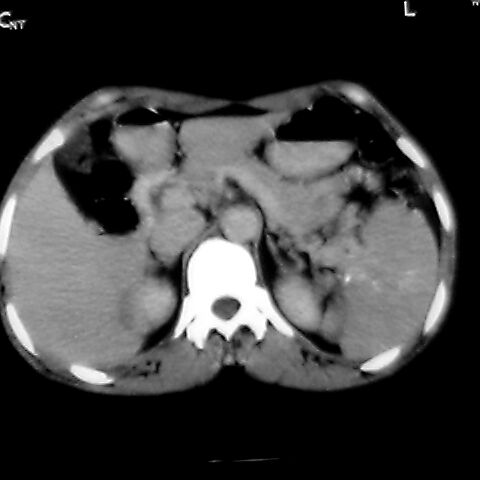

女 48岁 食道癌术前体检发现脾占位。

脾胀内部巨大低密度肿块,边界清或不清,中心坏死,轻度增强,内见散在钙化,结合食道癌病史多考虑:转移癌.

1肝右下叶小囊肿2右肾上极囊肿或错构瘤3脾脏不典型血管瘤可能性大.

脾脏低密度灶伴钙化,增强化明显,中心见液化坏死灶,强化延时明显。考虑血管瘤。转移瘤待排。

1,脾血管瘤。2,右肝,右肾小囊肿。